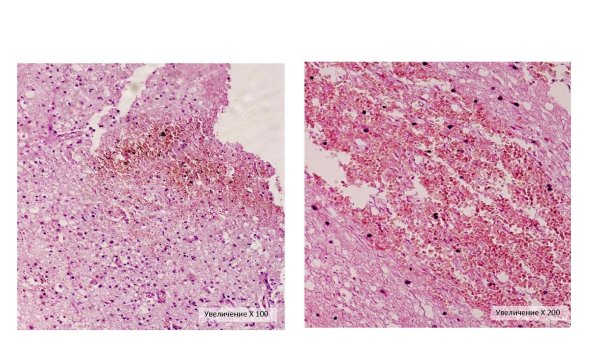

Геморрагический инфаркт легкого гематоксилин эозин

Геморрагический инфаркт легкого окраска гематоксилином

Геморрагический инфаркт легкого гистология

Геморрагический инфаркт легкого микропрепарат